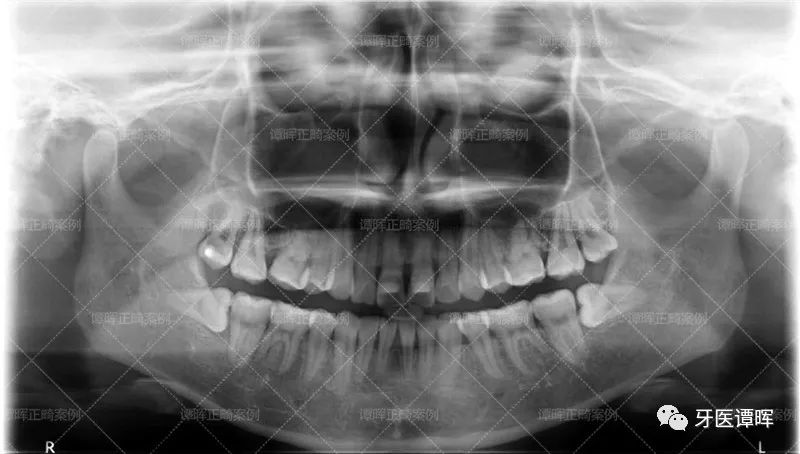

△X线分析:明显看出前牙往前突,上牙的侧切牙也是非常不齐。

从X线分析图可以明显看出前牙往前突内收,上牙的侧切牙也已排齐,牙列排齐。